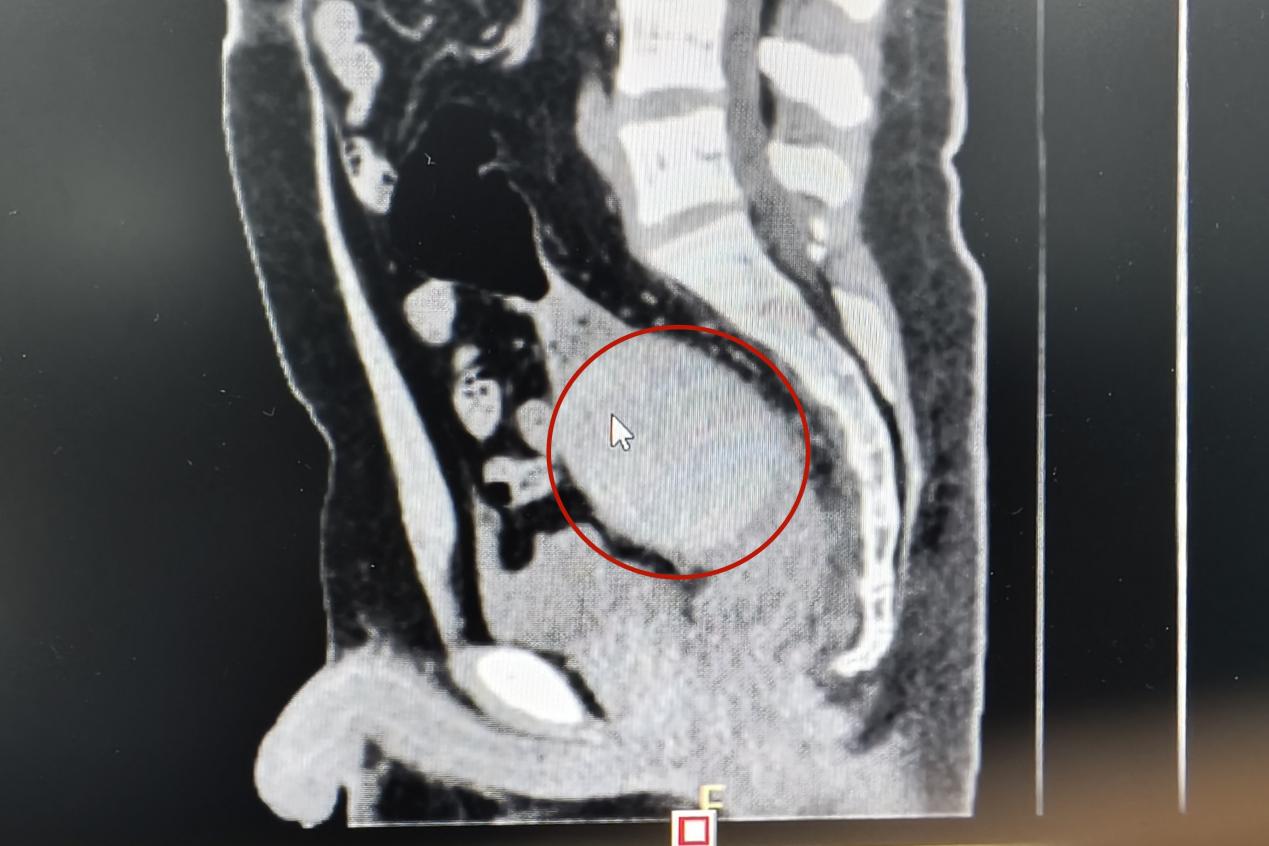

當(dāng)天下午,一名青年男子來(lái)到衡陽(yáng)市中心醫(yī)院肛腸外科門(mén)診就醫(yī),稱(chēng)肛門(mén)內(nèi)有異物,肚子疼得很。李祥樂(lè)仔細(xì)詢(xún)問(wèn)病情,男子卻總是支支吾吾??此?/span>表情痛苦,李祥樂(lè)便讓他躺到治療床上,對(duì)其進(jìn)行了肛門(mén)指檢。“你這個(gè)異物卡得很深,指檢觸不到,需要馬上做個(gè)CT明確位置。”李祥樂(lè)一邊告知患者一邊詢(xún)問(wèn),“這個(gè)東西卡進(jìn)去多久了?”得知是昨晚發(fā)生的事,李祥樂(lè)心頭一驚,卻表面平和地安慰患者道:“沒(méi)事的,到醫(yī)院來(lái)你就放寬心了,等檢查結(jié)果出來(lái)我們想辦法給你取”。CT結(jié)果顯示患者異物位于直腸與乙狀結(jié)腸交界處,位置特殊,加之卡頓時(shí)間長(zhǎng),取的過(guò)程中腸道破裂出血的風(fēng)險(xiǎn)隨之增加。“我可以嘗試給你經(jīng)肛門(mén)取,但是如果取不出來(lái)那就需要進(jìn)行腹腔手術(shù)了”。